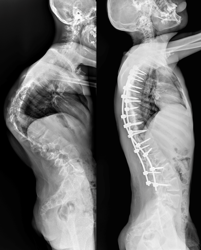

Врачи отделения травматологии и ортопедии РДКБ РНИМУ им. Н.И. Пирогова Минздрава России провели успешную операцию по коррекции кифосколиоза у пациента с синдромом Протея. Хирургическое вмешательство длилось более семи часов и было технически сложным: кифотическая деформация грудного отдела позвоночника составляла более 110 градусов, а комбинированная сколиотическая — по 90 градусов в грудном и поясничном отделах. Благодаря слаженной работе опытной команде хирургов удалось добиться существенной коррекции и обеспечить пациенту достойное качество жизни в будущем. По словам врачей, мальчик даже сможет заниматься своим любимым делом — кататься на велосипеде.

«К нам он поступил с уже существенным искривлением позвоночника. Кифотическая деформация грудного отдела составляла более 100 градусов, а сколиотическая — более 90 градусов в грудном и поясничном отделах. Отмечались нарушения походки, а совокупность этих и других проблем пациента, связанных с основным диагнозом, сильно влияла на его качество жизни», — отмечает Андрей Андреевич.

После операции Мурат быстро активизировался и восстанавливался. Хирургам удалось добиться невероятных результатов в коррекции: угол кифотической деформации был снижен до 60 градусов (практически вдвое), а сколиотических — до 40-50 градусов, обеспечен удовлетворительный баланс позвоночника в сагиттальной и фронтальной плоскостях.